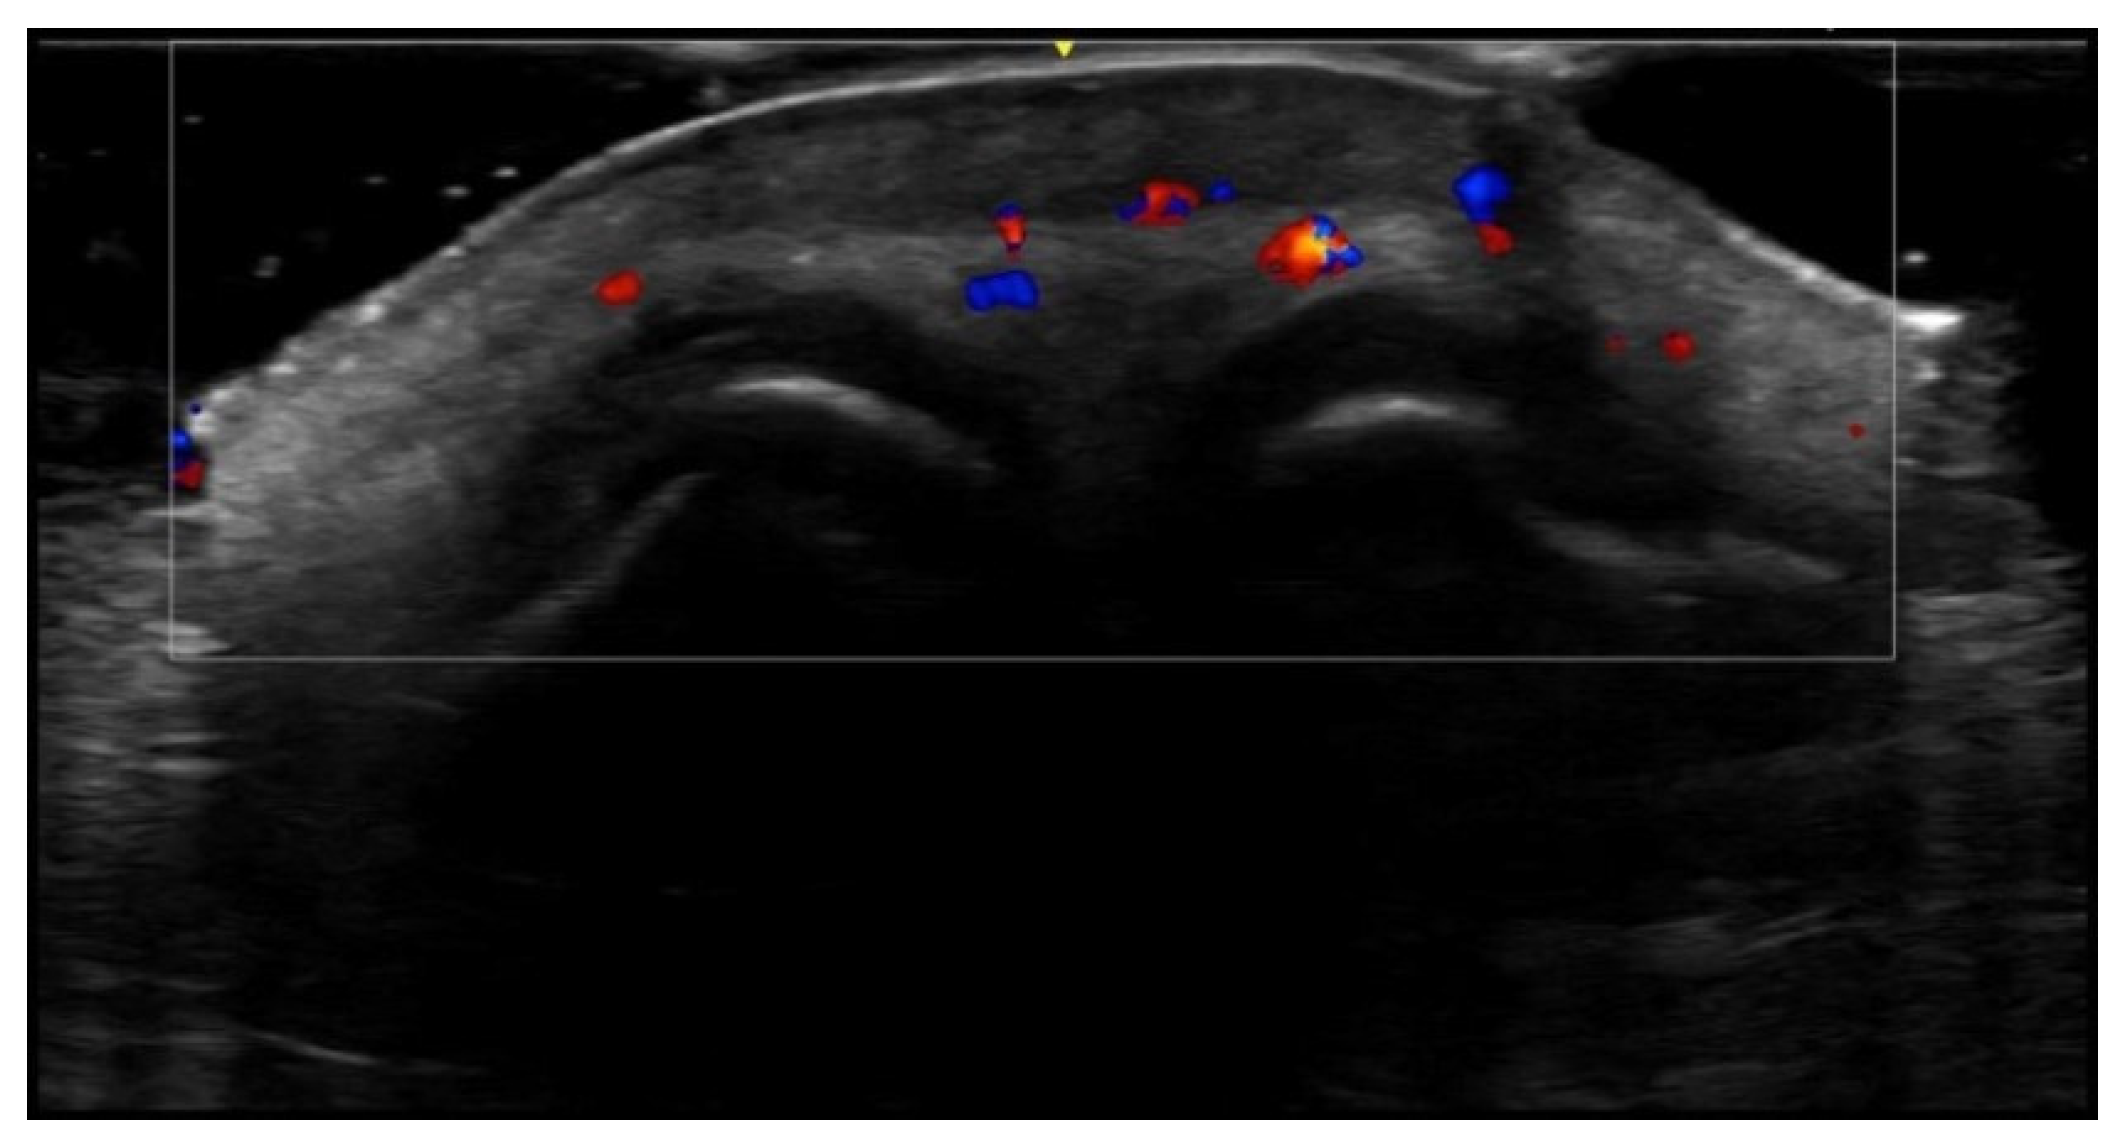

5. Specific Cutaneous Structure and Sites of Skin Disorders

6. Vascular Disorders